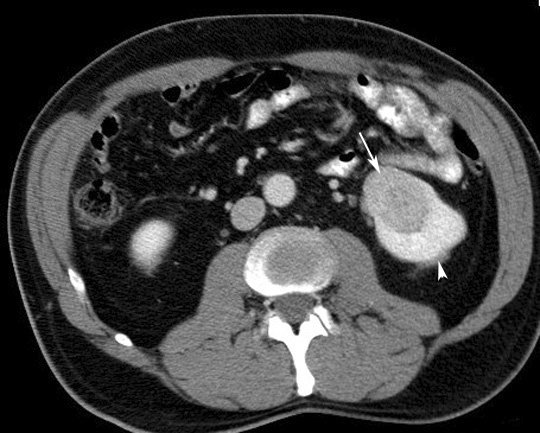

9. Renal Cancer

When malignant cells form in the tubules of the kidneys, renal cell cancer is said to develop. Renal cell cancer is also called renal adenocarcinoma. Humans have 2 kidneys, one on each side of the backbone. The tiny tubules have the responsibility of cleaning and filtering the blood and eliminating the waste products through urine formation.